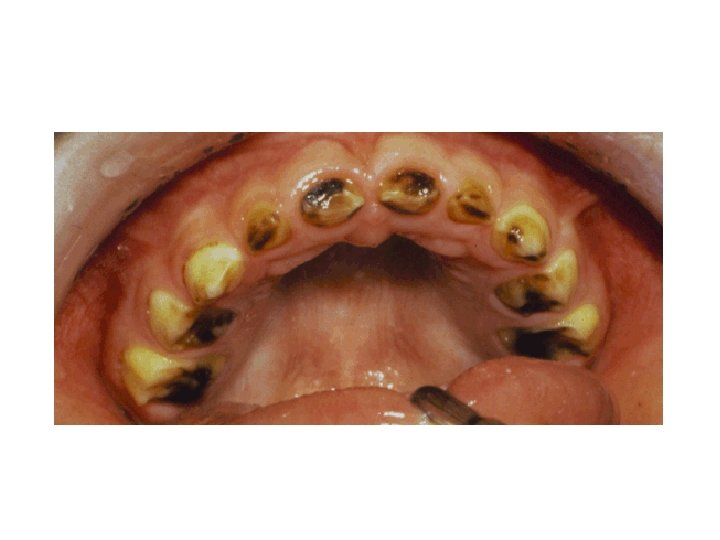

ACUTE DENTAL CARIES - Rapid clinical course & early pulp involvement - Process rapid little time for deposition of sec. dentin. Dentin stained a light yellow - Rampant caries, affecting deciduous dentition nursing bottle caries - Commonly 4 maxillary incisors followed by first molar and then cuspids - Absence of caries in mandibular incisors distinguished from ordinary rampant caries